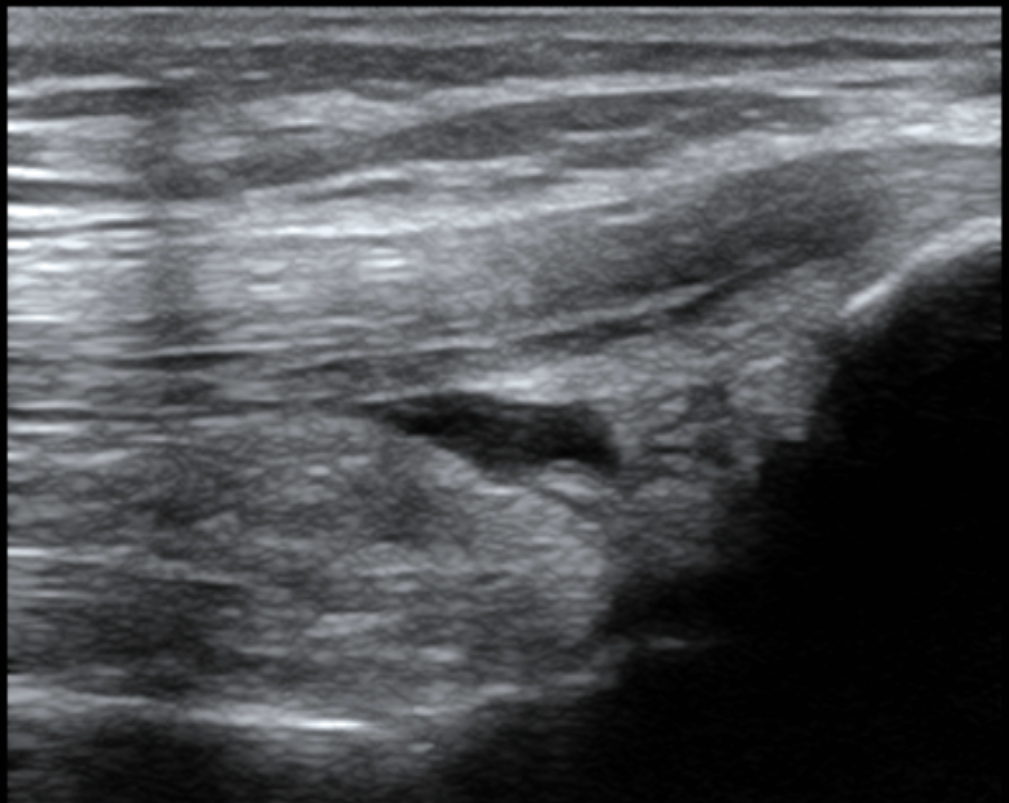

Ultrasound Image Analysis (2nd Photo): The dark areas in the scan indicate where the fluid has accumulated. This allows us to assess the volume and exact location of the effusion objectively.